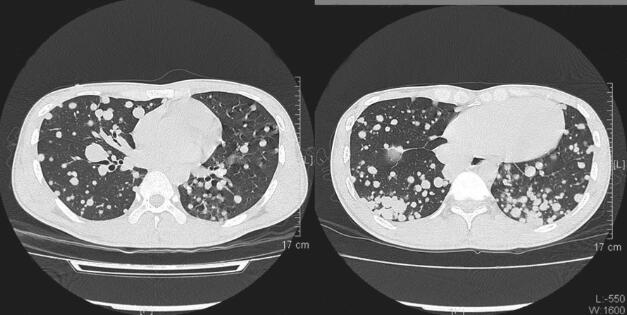

图2 肺部CT平扫:双肺多发转移瘤

入院查体未发现阳性体征。X线胸片(2014年3月12日)考虑双肺转移癌,建议进一步检查。高分辨率螺旋CT平扫:双肺弥漫性结节影,考虑转移(图1和图2)。血细胞分析(2014年3月12日)MPV 6.9fl↓。支气管镜检查示:气管腔内未见明显异常。灌洗液结核菌涂片:阴性。(2014年3月15日)气管镜刷片病理:“肺左下叶基底段”刷片见柱状上皮中性粒细胞,未查见瘤细胞。结核感染T细胞斑点试验(T-spot):阴性。支气管镜检TBLB病理回报:“左下肺基底段活检组织”送检肺组织间质见少许慢性炎细胞浸润、纤维化,血管玻璃样变,局灶肺气肿。入院给予左氧氟沙星抗感染治疗。因气管镜无阳性病理结果,患者往胸外科行外科胸腔镜检查,病理结果:“右肺下叶结节”符合神经内分泌肿瘤(副神经节瘤或神经内分泌癌等)。结合形态学(见特征性Zellballen结构,未见缎带、菊形团结构)及免疫组化结果[Vim(+)、CK(-)、CK7(-)、EMA(-)及TTF1(-)等]倾向于副神经节瘤,并见脉管内有瘤栓形成。请重点检查颈部、纵隔及腹膜后,行颈部血管彩超、纵隔CT均未发现有副节瘤原发灶,行18F-FDG体部断层显像肺部外未发现明显异常高代谢病灶。

2. 主要表现为反复咳嗽、咳痰伴间断咯血,查体双肺未闻及干湿性啰音,胸部CT检查提示双肺弥漫性结节影,考虑转移。